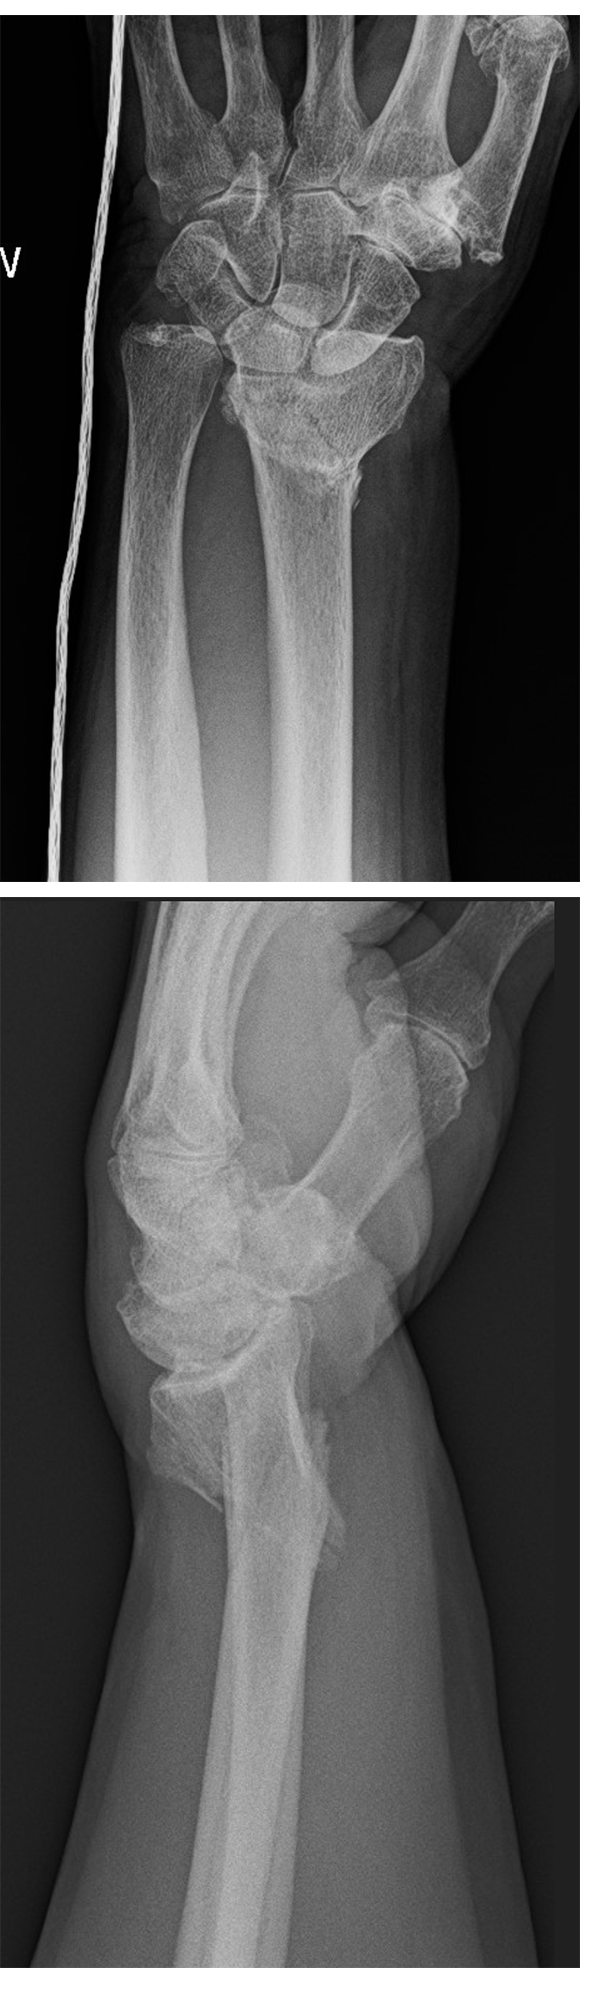

72 y. male, right hand dominant, fell from standing position onto left wrist. Following that, had immediate pain and unable to use left hand without discomfort. No other areas of pain, no head trauma, no loss of consciousness. Examination showed obvious wrist deformity and swelling with tenderness to palpation and intact neurovascular- specifically the medial nerve.

1. Describe the plain radiograph.

1. Plain radiograph of the left wrist of Mr X in AP and lateral projection, showing a distal end radius fracture which likely have intra-articular extension, loss of radial height and dorsal displacement and also present is an ulnar styloid fracture. There is no evidence of carpal bone fractures or any radiocarpal dislocation.

I would like to order other plain radiographs to assess the entire lenght of radius and ulnar and elbow in AP/Lat to make sure there are no other fractures +/- dislocation present.

1. Frykman classification

• 8 groups, (1,3,5,7 only radius involved; 2,4,6,8 with ulnar styloid, 1 to 4 no DRUJ, 5 to 8 got extension into DRUJ).

• takes into account ulnar styloid fracture

• takes into account if distal radius fracture involves the DRUJ

1. My management of this patient begins in ED.

at ED: After ensuring no open wounds at fracture site and no neurovascular injury is present, I would attempt a CMR of the fracture with patient under conscious sedation and apply a above elbow POP with 3 point fixation to stabilise the reduction, reassess fracture reduction with plain radiographs of the wrist (study fracture pattern more clearly, any SL ligament injury) as well as neurovascular status of the patient following reduction.

Why do CMR?

• to visualise fracture pattern better.

• to reduce soft tissue injury by fracture ends

• in case cannot do operation soon

Overall, this is an unstable fracture pattern with potential for displacement once soft tissue swelling subsides. I would counsel my patient for surgery- open reduction and internal fixation.